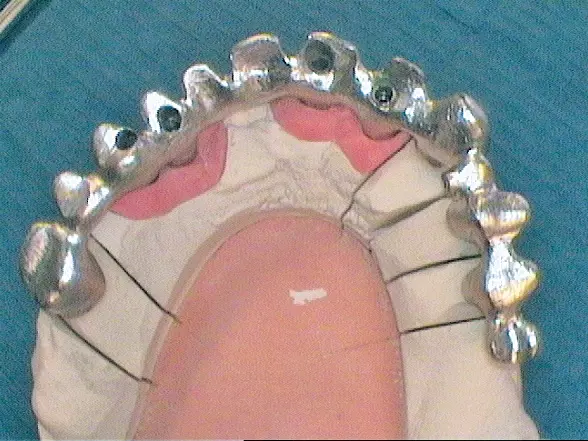

Nach Freilegung der Implantate regio 026,027 im Februar 2020, bei der auch die Implantation regio 037 (T3, Zimmer Biomet Dental, 4,0 mm x 13,0 mm) vorgenommen wurde (Abb. 32 OPG nach Freilegung), erfolgte im März nach Abformung mit offenem Löffel (open tray technique) und Gesichtsbogenregistrat die prothetische Versorgung mittels CAD/CAM gefräster Abutments (Dentaltechnik Hessel und Lutgen, Trier) und transversal verschraubter, verblockter VMK-Kronen (Abb. 33-36). Die Freilegung und Versorgung des Implantates 037 ist zusammen mit der Entfernung des Zahnes 38 für Juli 2020 geplant.